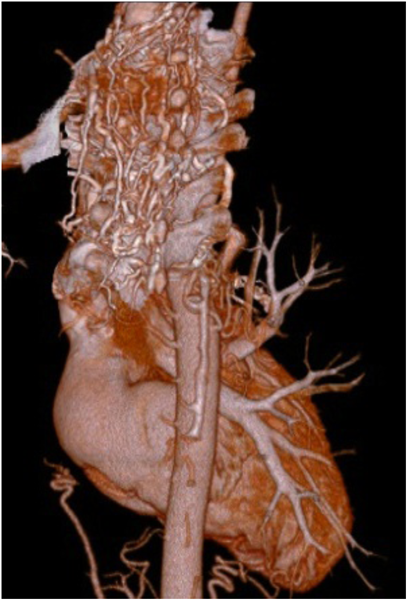

2)末梢血管異常

血液粘稠度増加によるshear stressにより,血管内皮細胞から産生された一酸化窒素やプロスタグランディンを介して血管の拡張・蛇行が出現する.また慢性的な低酸素により末梢血管,毛細血管が新生あるいは増生する(図3).

Pediatric Cardiology and Cardiac Surgery 31(3): 95-101 (2015)

図3 後縦隔でみられる動脈の増生

冠動脈でも同様に血管の拡張・蛇行,新生血管の増生がみられるが,冠血流予備能は低下する(図4, 5).